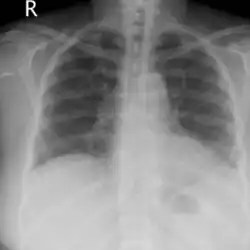

Acute pulmonary edema due to salt water aspiration syndrome

Recovery after 48 hours of supplemental oxygen

Chest x-rays of a 61-year-old female who developed salt water aspiration syndrome while swimming during a triathlon.[5]

Lung auscultation may reveal abnormal breath sounds such as rhonchi (snoring-like) or crackles (rattling), and chest imaging can show lung consolidations[4] and edema.[5] Decreased lung volumes, including a reduction of average 0.7 liters in forced expiratory volume in 1 second and vital capacity, is found on spirometry. Laboratory studies do not show specific abnormalities, but low oxygen levels in blood, slightly elevated white blood cell count and lactate dehydrogenase levels may be seen.[1]